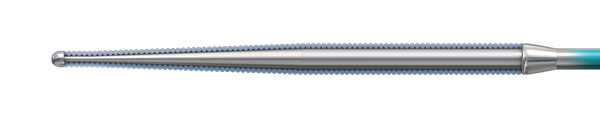

Micro EMTTM Technology

MICRO EMT exactly matches the taper of the core and coil, allowing for a lower profile and a more flexible core, leaving almost no room for the core to move within the coil, resulting in 1:1 torque.

- Entry: The smallest tip on the market (0.008”) and the long taper (6 cm) facilitate easy lesion entry in even the most complex lesions.

- Maneuverability: A flexible distal shaft enables excellent intraluminal navigation in complex lesions, with minimal perforation risk.

- Torque: With exactly matched tapers, the core and coil move as one, eliminating whip and empowering precise steerability.